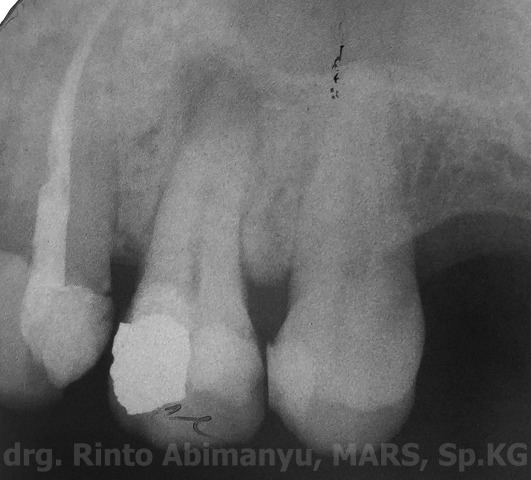

dan ini ronsennya…

Radiografis setelah selesai perawatan

Alhamdulillah seluruh perawatan telah selesai, tetapi tetap pasien saya ingatkan untuk pembuatan crown mengingat sisa struktur asli gigi pada bagian bukal dan palatal sudah tipis… Mudah2an sampai ketemu di pembuatan crown restorasinya masih aman.. aamiiin.. 🙂